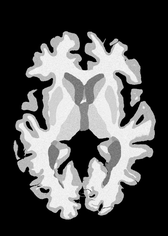

4.2 Registration to a 100 micron ex-vivo brain MRI volume

To showcase the efficacy of our method on real large scale images, we register a 250 in-vivo MRI image (Lüsebrink et al., 2017) to a 100 ex-vivo FLASH human brain volume (Edlow et al., 2019). This represents an inverse problem with more than 11.2B optimizable parameters (compared to 20M for clinical datasets), or 44.8GB of GPU memory. The entire problem does not fit on most GPUs, necessitating distributed multimodal registration. We optimize a composite transform - affine followed by a diffeomorphic mapping; details can be found in Section E.1. Multimodal deformable registration took 58 seconds on 8 NVIDIA A6000 GPUs, which is unprecedented at this resolution. Fig. 6 shows qualitative results, highlighting the ability to register highly detailed structures such as cerebellar white matter; these structures are not visible at macroscopic scales. The resultant advantages of performing registration at this scale can allow researchers to characterize the neuroanatomy at microscopic resolutions and allow morphometric analysis of cortical layers and subcortical nuclei among other structures.